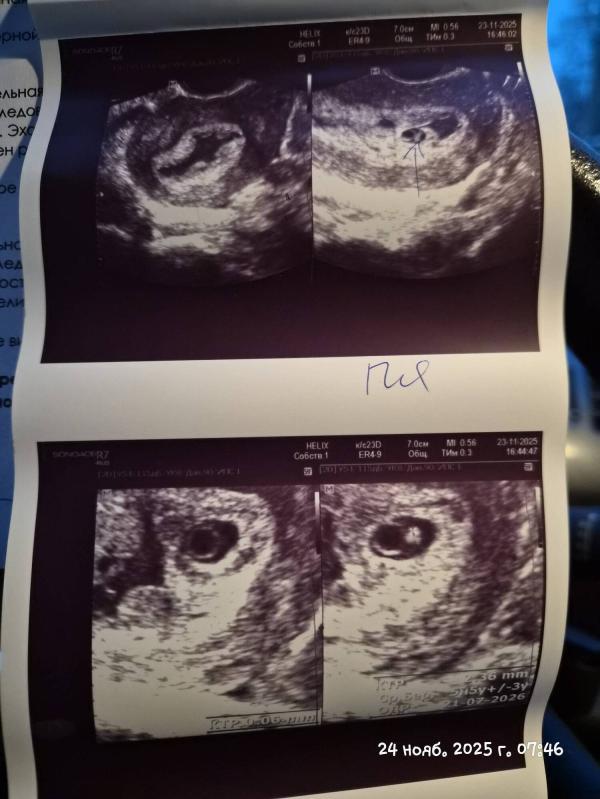

Вчера была на узи. По месячным у меня 6 недель 5 дней было. Но, что и требовалось доказать, овуляция была поздней и по узи нам 5-6 недель. В полости матки лоцируется округлое плодное яйцо правильной формы: средний диаметр= 8.7 мм (что соответствует 5 нед 5 дн беременности). В полости яйца лоцируется желточный мешок 4.0 мм с 1 эмбрионом, КТР= 2.36, что соответствует 5 нед 5 сут беременности/+/- 3 сут. ЧСС регистрируется.

НО снова гематома, каждая беременность у меня начинается с гематомы. Может кто знает, почему такое может быть?